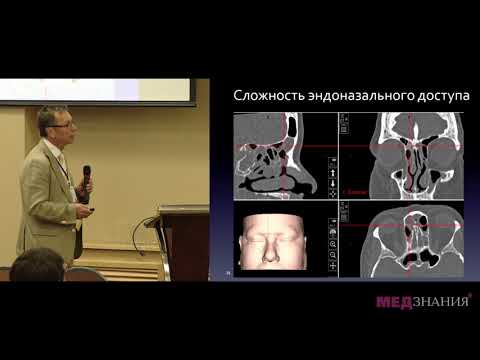

КТ околоносовых пазух. Что такое остеома?

Эндоскопическое удаление остеомы лобной пазухи

Если остеома оказывает давление на окружающие структуры, могут понадобиться дополнительные исследования, такие как КТ или МРТ.

Хирургия лобной пазухи. Лопатин А.С.